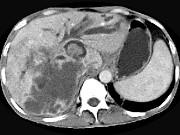

问题 男,44岁,右上腹痛半年,腹部未触及包块,轻度黄疸,AFP阴性,CT检查如图,最可能的诊断为()

选项 A.原发性肝癌 B.胆管细胞癌 C.肝囊肿 D.肝脓肿 E.肝血管瘤

答案 B